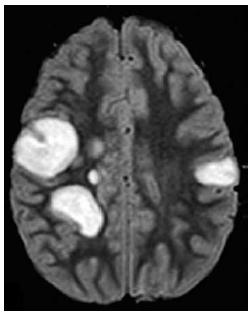

Garota de 13 anos de idade com diagnóstico recente de insuficiência renal crônica apresenta episódio de cefaleia, turvação visual e crise epiléptica tônico-clônica generalizada. A pressão arterial é de 180 x 100 mmHg. A ressonância magnética de crânio demonstra o achado a seguir.

Enunciado 3043514-1

O diagnóstico mais provável é

Menina de 9 anos de idade é levada ao pronto-socorro por sonolência e fraqueza muscular progressivas há 2 dias. Na avaliação, a criança se apresenta sonolenta, mas desperta aos estímulos vigorosos. Não responde aos comandos solicitados. Reflexos osteotendíneos são exaltados globalmente, e apresenta reflexo cutâneo plantar em extensão à esquerda e sem resposta à direita. O reflexo pupilar e o exame de fundo de olho são normais. Há 10 dias do início dos sintomas, ela apresentou quadro de infecção de vias aéreas superiores, a qual foi tratada com amoxicilina.

A imagem da ressonância magnética de crânio é mostrada a seguir.

Enunciado 3043506-1